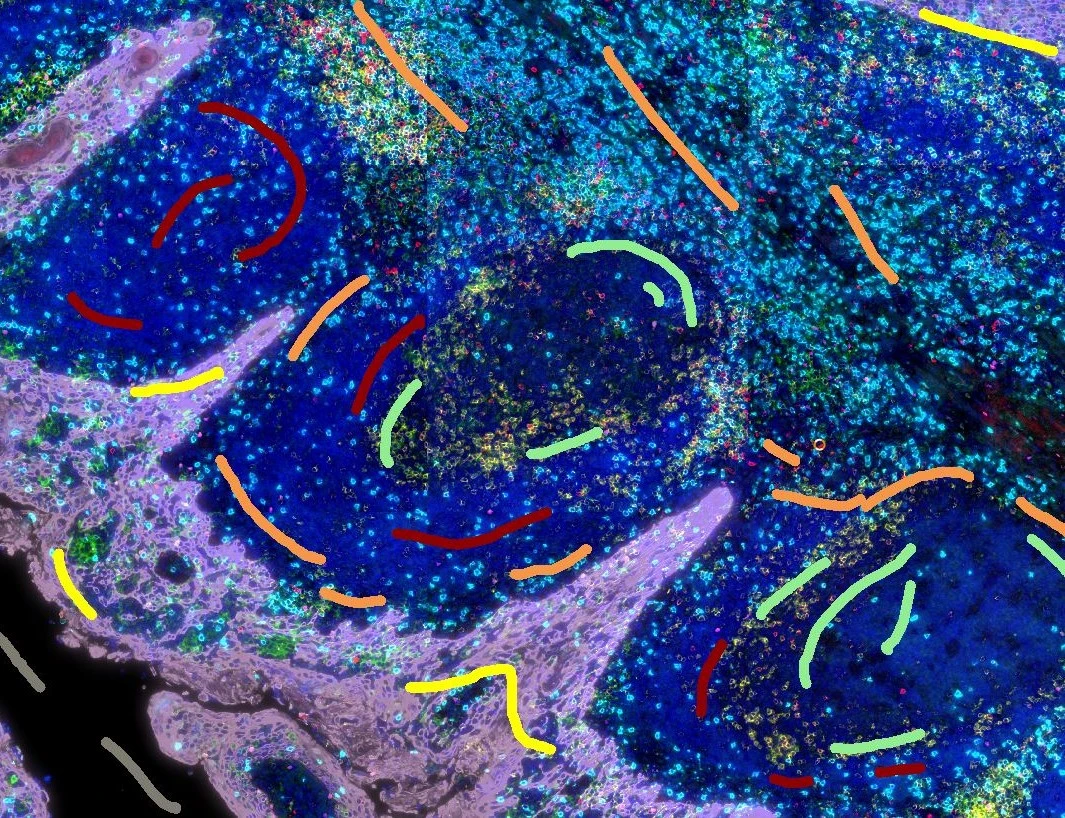

IHC Immune Status in Situ

Segment tissue into tumor, stroma, and lymphocyte clusters using an AI classifier, detect hematoxylin-stained nuclei and immune phenotypes (e.g., CD45, CD3, CD20), and quantify spatial immune distribution.

bladder cancer, CD45, immune cells, tumor immune microenvironment, tertiary lymphoid structures, spatial analysis

The IHC Immune Status in Situ App is segmenting the tissue sections in morphological entities such as tumor, stroma and lymphocyte clusters using the AI Classifier. It furhter identifies single cells based on nuclei staining (hematoxylin) and detects immune cells based on appropriated stains (CD45, CD3, CD20 etc.). It also measures the distance of detected objects to the metastructure boundary, distance ranges can be defined. The App outputs parameters including area of the detected morphological entities, number/percentage of lymphocytes detected with the tissue entities as well as in certain proximities of the entities.

Original Image

Tumor/Stroma/lymphoid cluster detection

Proximity map tumor

Proximity map lymphoid cluster